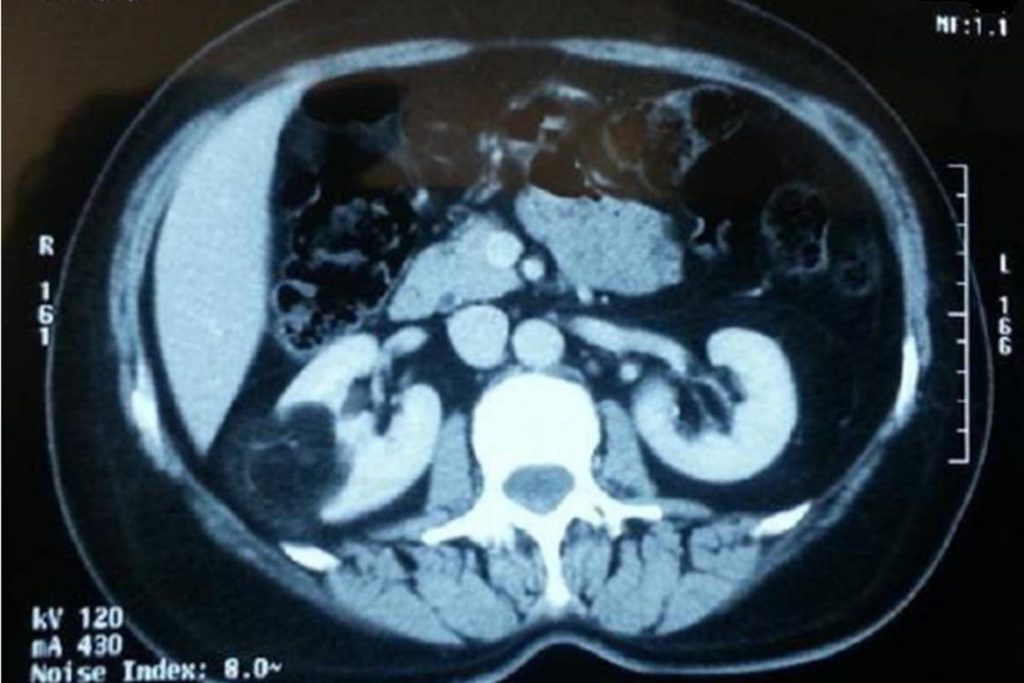

The study evaluated abdominal CT scans performed on adult patients and observed that a substantial number of cases presented with simple renal cysts — fluid-filled sacs located within the kidneys. These cysts were not associated with any urological symptoms or underlying kidney conditions.

- The majority of cysts were classified as Bosniak category I, indicating simple cysts with benign characteristics.

The researchers concluded that most incidental renal cysts are clinically insignificant and do not require further diagnostic procedures or follow-up. However, complex or atypical cysts may warrant closer observation through advanced imaging techniques such as contrast-enhanced CT or MRI.